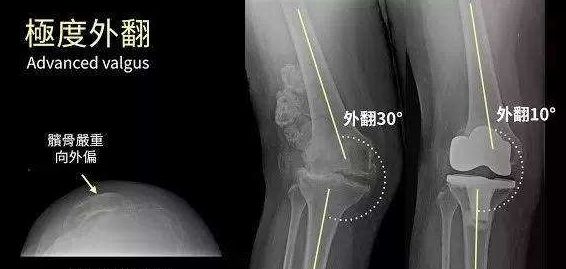

3、有髌骨外翻问题的人,因为髌骨先天不稳定,常爬楼梯或爬山会使外翻问题更严重。